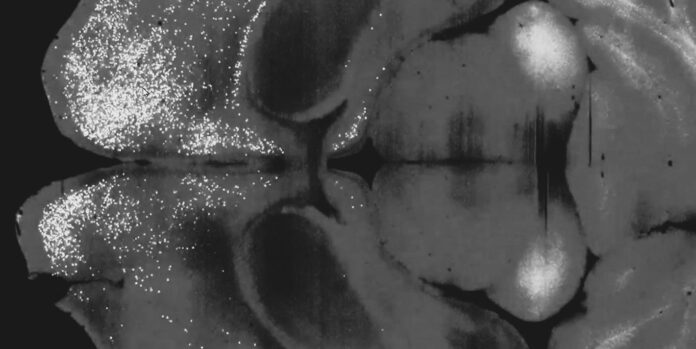

First the researchers injected a single dose of psilocybin into a mouse’s frontal cortical pyramidal neurons. Then a day later, they chased it with a variant of the rabies virus that could transmit across a synapse and label those connected neurons with fluorescent proteins. After the virus had incubated in the mouse for a week, the team imaged its brain and compared the results with a control mouse brain that had only received the virus.

The fluorescent tagging revealed that psilocybin had weakened recurrent connections within the cortex – feedback loops that may explain why a depressed person fixates on negative thoughts.